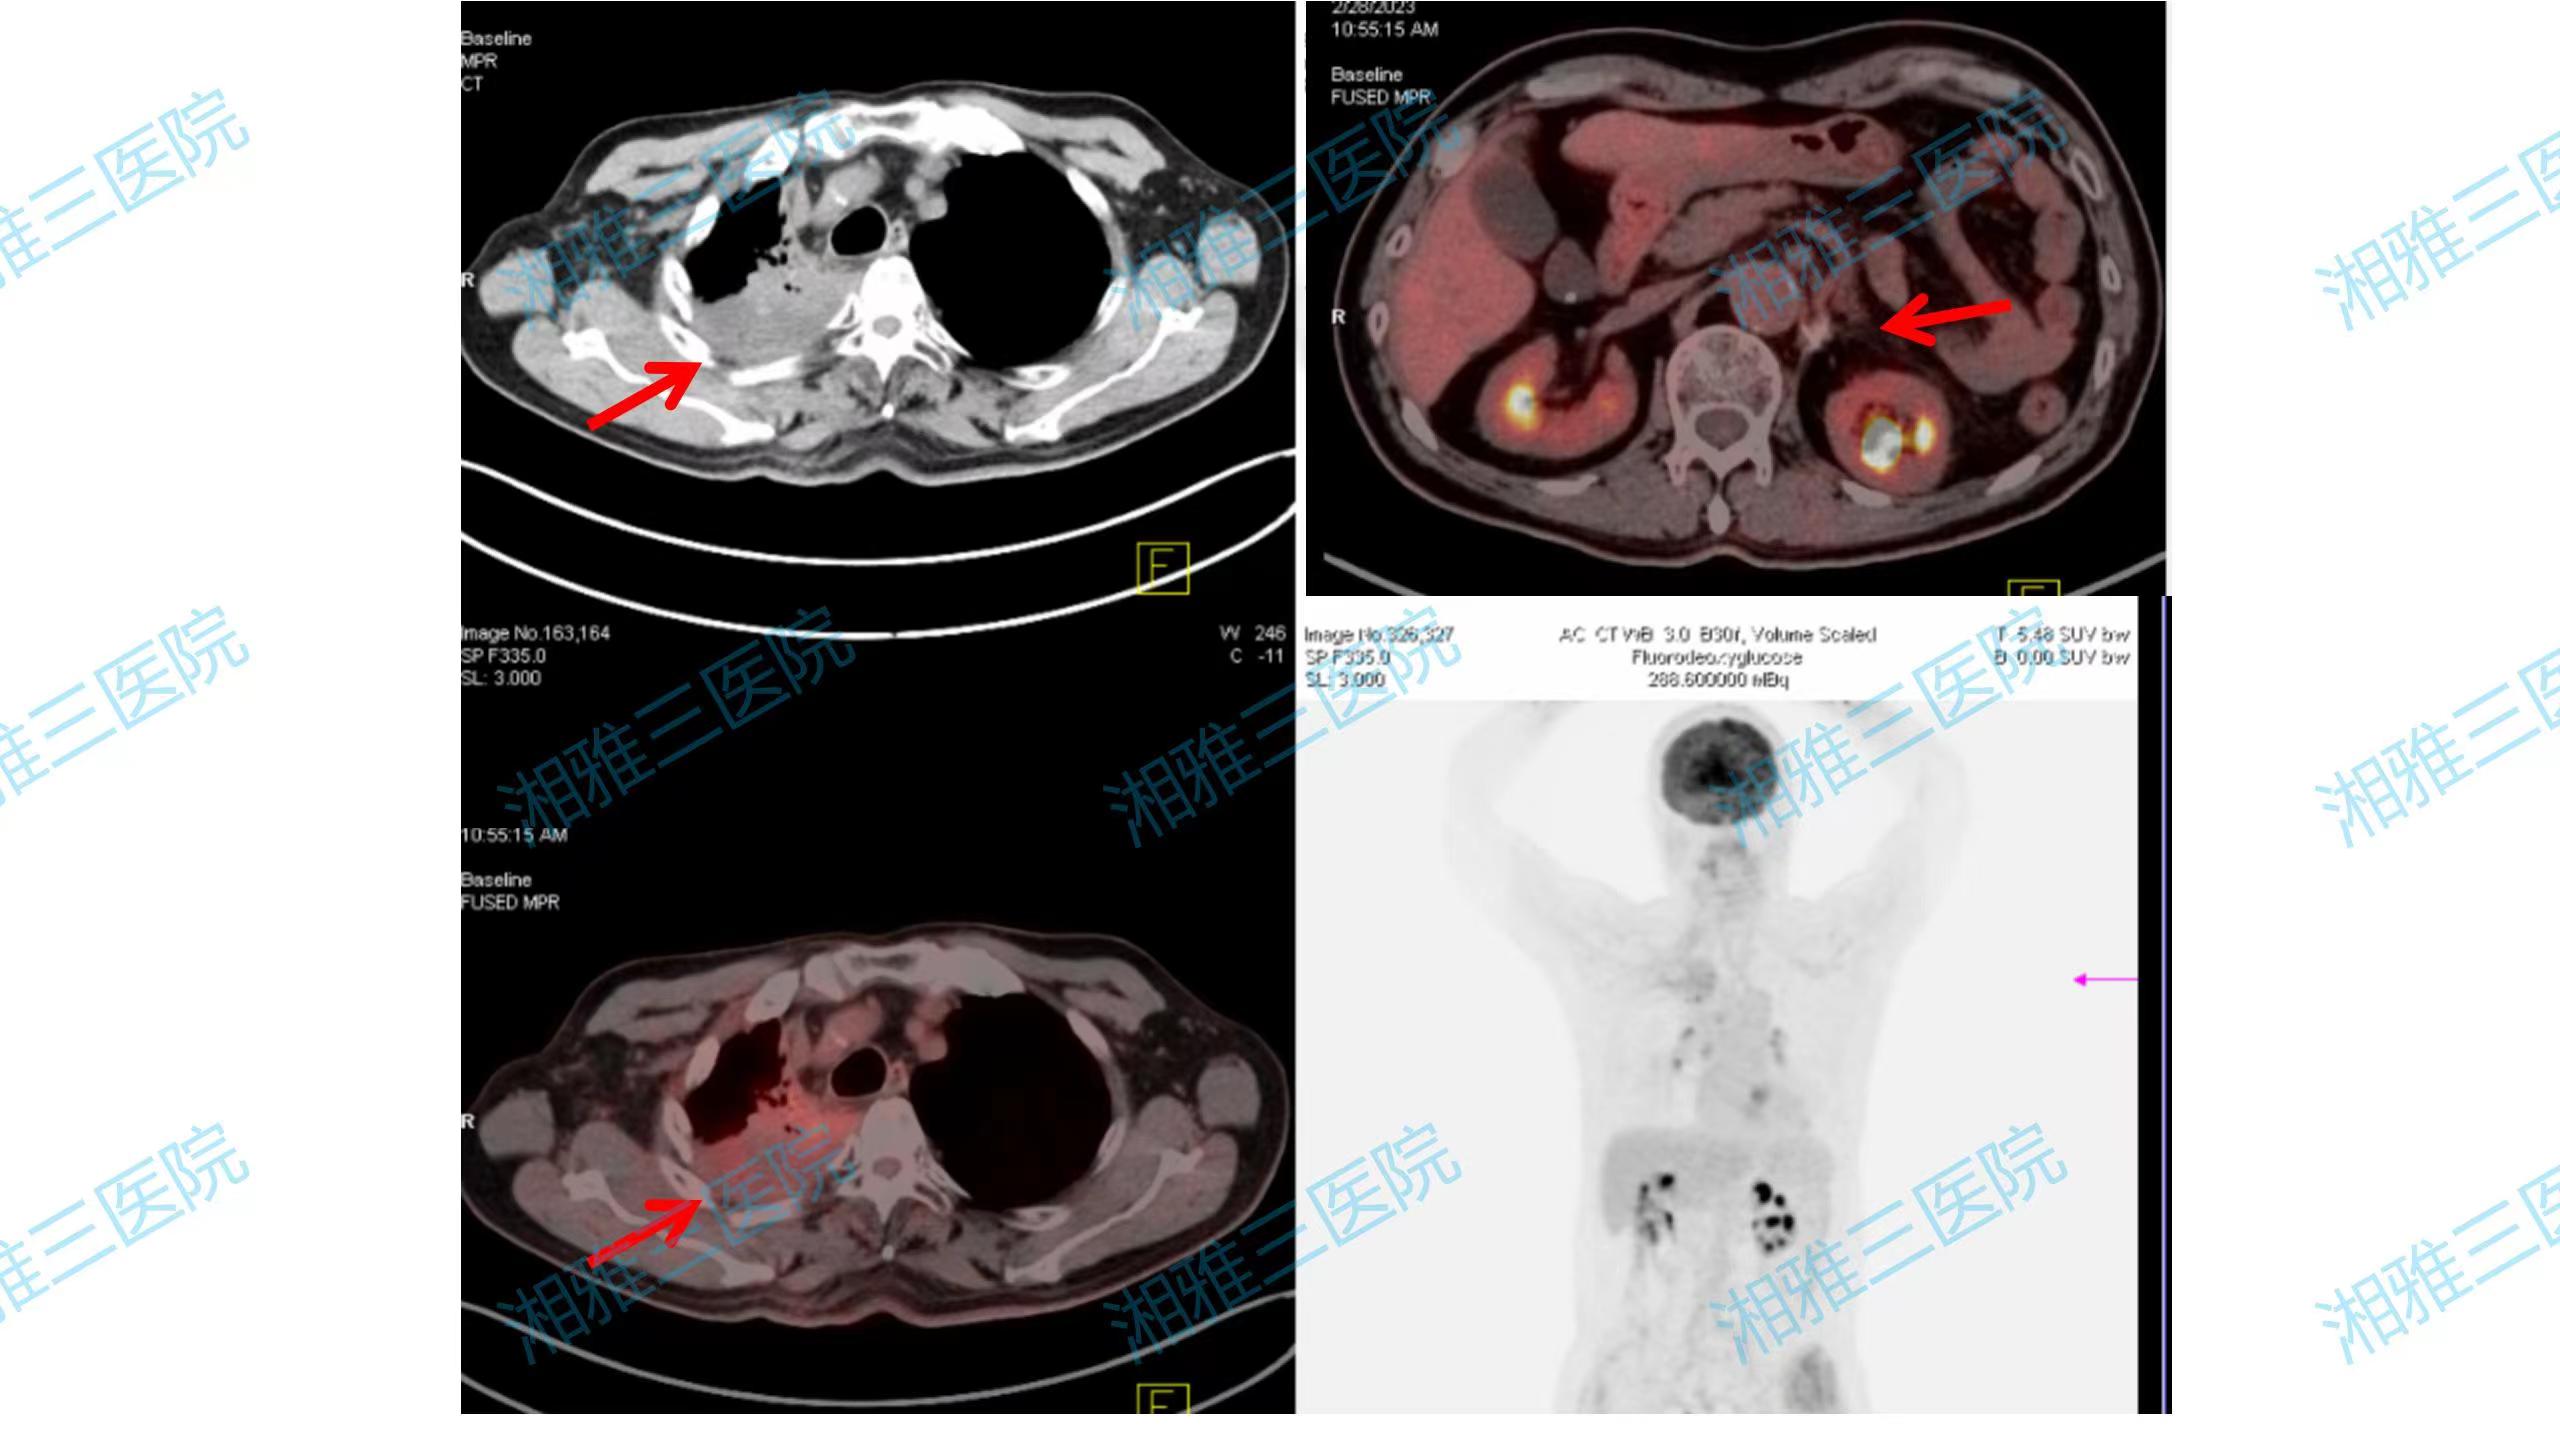

2020年7月,经过2周期系统药物治疗后,刘叔叔胸痛症状基本消失,影像学评估示肿瘤显著缩小。因右上肺肿块侵犯第1、2肋骨,手术创伤过大,经MDT讨论评估及刘叔叔和家属要求,不考虑手术切除,施行右上肺原发灶IMRT放疗,同步完成第3-4周期化疗联合免疫治疗。完成4周期化疗联合免疫治疗及原发灶放疗后,刘叔叔接受了培美曲塞联合免疫维持治疗。2020年10月接受了左肾上腺转移灶切除术,术后刘叔叔继续规律接受培美曲塞联合免疫维持治疗。然而,2021年5月复查提示左侧肾上腺转移灶复发。刘叔叔哽咽着回忆:“当时我自己都快放弃了,这个病反反复复估计是好不了,但是刘教授还是没有放弃让我彻底治好的机会。”经治疗组讨论,刘叔叔于2021年6月接受左肾上腺术后转移灶的SBRT放疗,放疗后继续接受培美曲塞联合免疫维持治疗,2022年3月开始减掉化疗,接受免疫单药维持至今。整个治疗期间多次复查,肺部及肾上腺转移灶均控制良好。

图3. 2023年3月刘叔叔完成PET/CT检查,提示:右上肺病灶治疗后纤维化,无代谢活性,全身无其他转移病灶,实现临床完全缓解。